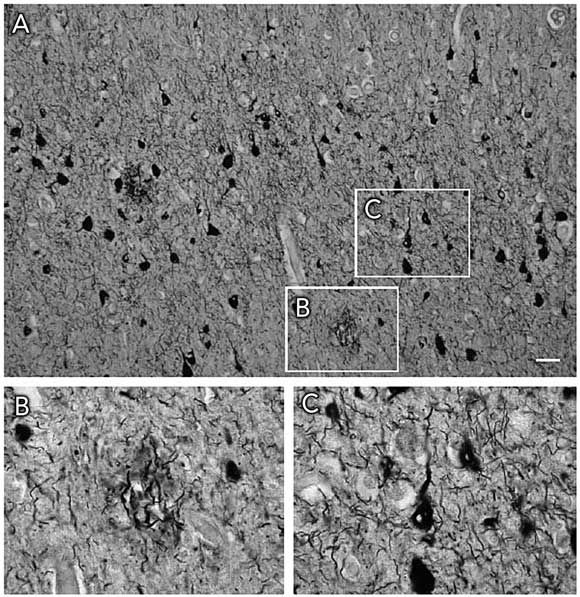

Histopathologically, both AD and FTD are characterised by insoluble filamentous aggregates in the brain (Box 1). They share this feature with Parkinson’s disease and Creutzfeldt–Jakob disease. The biological basis of AD and FTD is discussed in Box 2. As both diseases involve lesions containing the microtubule-associated protein tau, they are classed as tauopathies (see Box 3 for definitions). AD is characterised histopathologically by Aβ-containing amyloid plaques and tau-containing neurofibrillary tangles, whereas FTD exhibits neurofibrillary tangles alone.

AD is characterised histopathologically by Aβ-containing amyloid plaques and tau-containing neurofibrillary tangles, whereas FTD exhibits neurofibrillary tangles alone.